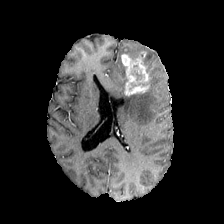

Diffusion models have shown impressive performance for generative modelling of images. In this paper, we present a novel semantic segmentation method based on diffusion models. By modifying the training and sampling scheme, we show that diffusion models can perform lesion segmentation of medical images. To generate an image specific segmentation, we train the model on the ground truth segmentation, and use the image as a prior during training and in every step during the sampling process. With the given stochastic sampling process, we can generate a distribution of segmentation masks. This property allows us to compute pixel-wise uncertainty maps of the segmentation, and allows an implicit ensemble of segmentations that increases the segmentation performance. We evaluate our method on the BRATS2020 dataset for brain tumor segmentation. Compared to state-of-the-art segmentation models, our approach yields good segmentation results and, additionally, detailed uncertainty maps.